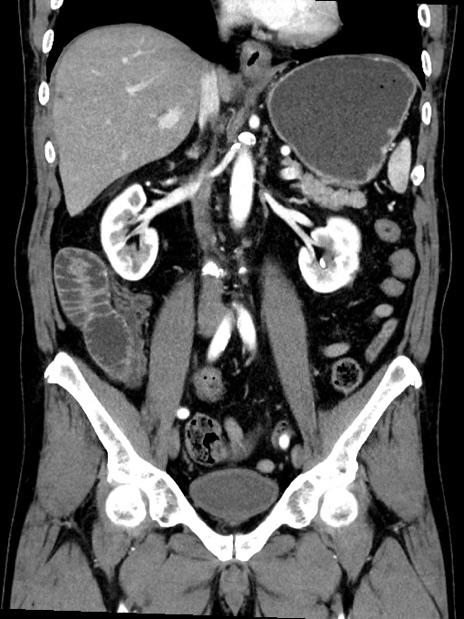

症例35(冠状断像)

【症例】70歳代 男性

【主訴】腹部膨満、嘔吐

【現病歴】昨日より腹部膨満感出現。本日増悪し、仙痛出現。嘔吐あり、受診。

【既往歴】糖尿病、胆摘後

【身体所見】BP 149/80mmHg、HR 74/min、BT 35.9℃、腹部:膨満、軟、圧痛なし。腸雑音減弱あり。上腹部正中切開瘢痕あり。

【データ】WBC 13500、CRP 1.72